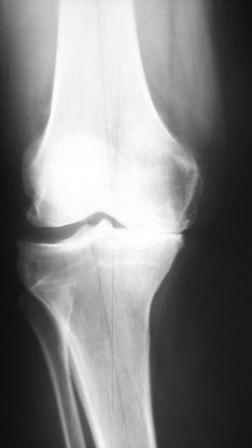

Глядя на снимки, кроме оперативного лечения в голову ничего не приходит. Хотя бы корригирующая кортикотомия б/б кости с минимальной внешней фиксацией. Высылаю пример.

На последнем фото внешний вид больной на завершающем этапе лечения (30 сутки) с трансформацией АВФ из гибридного в стержневой. Боль уходит сразу после операции. При данной Р-картине консервативно показано применение только обезболивающих препаратов - трамадол до 3 мес. по 100-200 мг в сутки, возможно внутрисуставное введение морфина 1,0 мл. При скрыто протекающем синовиите добавляются НПВС. Кроме того, должна помочь остеорефлексотерапия - в/костной иглой пункция проксимального метафиза б/б кости с введением 1,0-0,5 мл. физ.р-ра или новокаина. Возможе и вариант расширенного вмешательства по Беку: узким долотом через кожный разрез в 3-4 мм делается «прокол» кортикального слоя и маятникообразными движениями разрушается костный мозг. Боль проходит практически всегда и надолго.